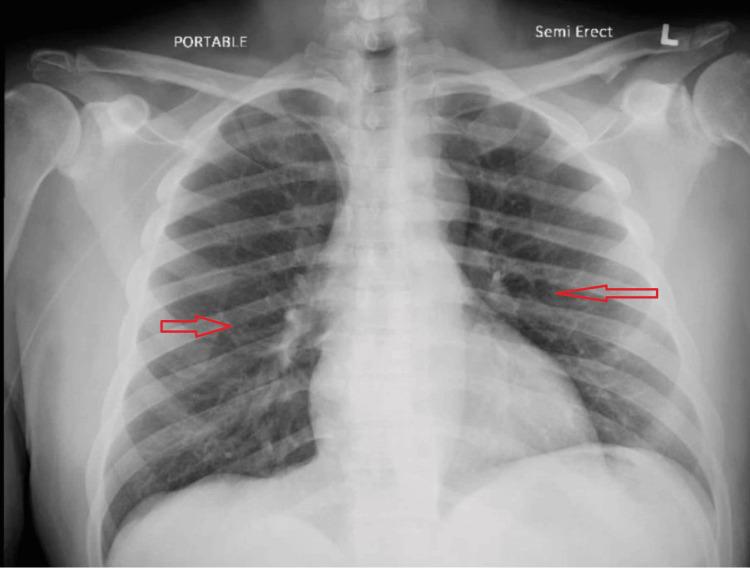

Pulmonary infiltrates, arising from diverse etiologies such as infections, cardiac conditions, or parenchymal diseases, present a diagnostic challenge. Drug-induced pneumonitis, although less common, should be considered, especially when symptoms develop after medication initiation. This case report highlights a rare yet significant complication of antibiotic therapy, daptomycin-induced eosinophilic pneumonia (DIEP). A 56-year-old male with a history of type 2 diabetes mellitus, hypertension, and renal insufficiency presented with pleuritic chest pain and a productive cough for two days. Chest X-ray and CT imaging revealed bilateral scattered airspace opacities and ground-glass opacities, suggesting pneumonia or pulmonary edema. Initially treated for healthcare-associated pneumonia, the patient's condition persisted despite therapy. His medical history included osteomyelitis treated with vancomycin, later switched to daptomycin. Two weeks after the switch, the patient developed new respiratory symptoms. A bronchoalveolar lavage (BAL) was performed to establish the diagnosis of eosinophilic pneumonia. BAL showed >25% eosinophils, confirming daptomycin-induced eosinophilic pneumonia. The antibiotic was discontinued, and prednisone 40 mg daily was initiated, leading to the resolution of symptoms. Daptomycin, an antibiotic commonly used to treat gram-positive infections, can rarely cause eosinophilic pneumonia, a rare adverse reaction characterized by pleuritic chest pain, dyspnea, and diffuse ground-glass opacities on imaging. The mechanism remains unclear but may involve surfactant binding, leading to alveolar epithelial injury. Diagnosis is confirmed through BAL, with eosinophilia greater than 25%. Management consists of discontinuing daptomycin and initiating steroids if necessary. This case underscores the importance of early recognition and prompt discontinuation of the offending drug, along with the use of steroids in cases with severe symptoms. BAL is a key diagnostic tool in confirming drug-induced eosinophilic pneumonia. In conclusion, daptomycin-induced eosinophilic pneumonia is a rare but significant complication requiring vigilance in patients treated with the drug. Early diagnosis and effective management are crucial for achieving favorable outcomes.

肺部浸润由多种病因引起,如感染、心脏疾病或实质性疾病,这给诊断带来了挑战。药物性肺炎虽不太常见,但也应予以考虑,尤其是在用药后出现症状的情况下。本病例报告强调了抗生素治疗一种罕见但严重的并发症,即达托霉素诱导的嗜酸性粒细胞性肺炎(DIEP)。一名56岁男性,有2型糖尿病、高血压和肾功能不全病史,出现胸膜炎性胸痛和咳痰2天。胸部X线和CT成像显示双侧散在的气腔实变和磨玻璃影,提示肺炎或肺水肿。最初按医疗保健相关肺炎进行治疗,尽管进行了治疗,患者病情仍持续。他的病史包括用万古霉素治疗的骨髓炎,后来改用达托霉素。换药两周后,患者出现了新的呼吸道症状。进行了支气管肺泡灌洗(BAL)以确诊嗜酸性粒细胞性肺炎。BAL显示嗜酸性粒细胞>25%,证实为达托霉素诱导的嗜酸性粒细胞性肺炎。停用抗生素,并开始每日服用40mg泼尼松,症状得以缓解。达托霉素是一种常用于治疗革兰氏阳性感染的抗生素,很少会引起嗜酸性粒细胞性肺炎,这是一种罕见的不良反应,其特征为胸膜炎性胸痛、呼吸困难以及影像学上的弥漫性磨玻璃影。其机制尚不清楚,但可能涉及表面活性剂结合,导致肺泡上皮损伤。通过BAL确诊,嗜酸性粒细胞增多大于25%。处理措施包括停用达托霉素,必要时开始使用类固醇。本病例强调了早期识别和及时停用致病药物的重要性,以及在症状严重的病例中使用类固醇的重要性。BAL是确诊药物性嗜酸性粒细胞性肺炎的关键诊断工具。总之,达托霉素诱导的嗜酸性粒细胞性肺炎是一种罕见但严重的并发症,在用该药物治疗的患者中需要保持警惕。早期诊断和有效管理对于取得良好预后至关重要。